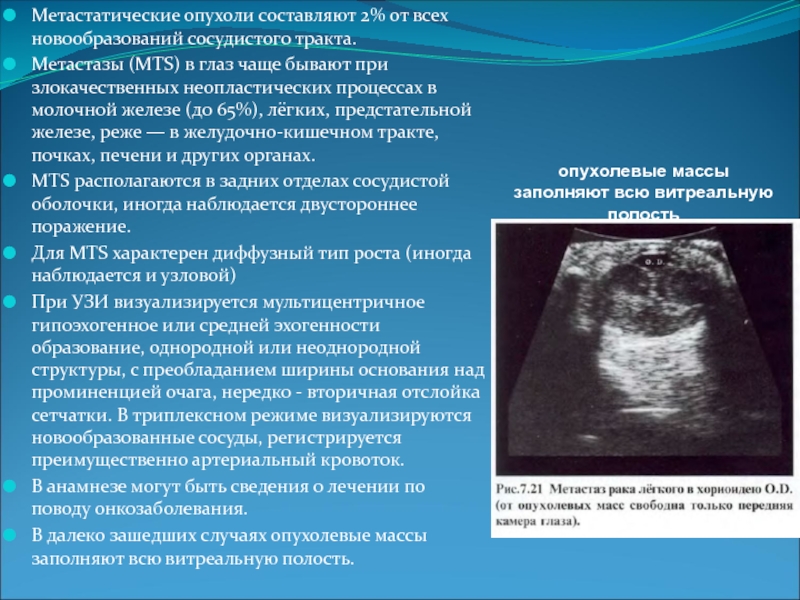

Метастатические поражения печени в ультразвуковом изображении характеризуются